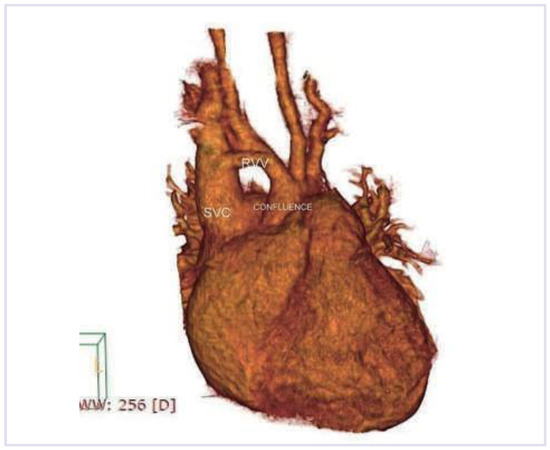

The fact that non-valvular (non-rheumatic) atrial fibrillation creates detectable thrombi in 17% of patients without oral anticoagulation and that 16% of the 17% (over 90% relatively) reside in the left atrial appendage (LAA), suggest that patients w...